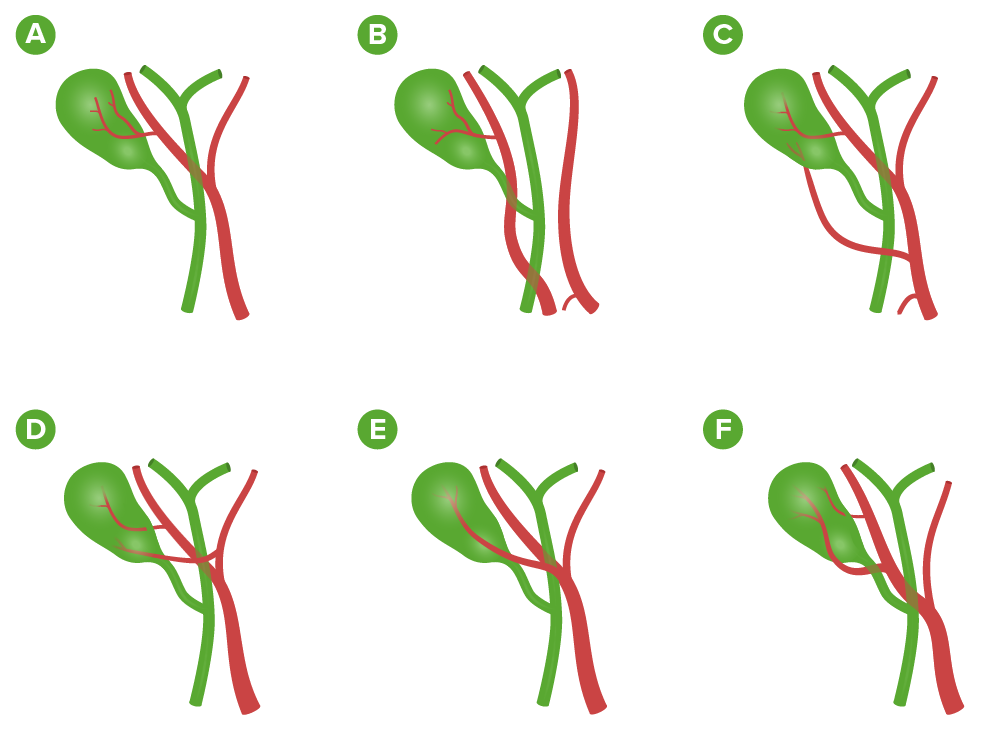

- Arteria cística:

- De la arteria hepática derecha (más común)

- De la arteria hepática derecha que surge de la arteria mesentérica superior

- 2 arterias císticas: de la arteria hepática derecha y hepática común

- 2 arterias quísticas: de las arterias hepáticas derecha e izquierda

- Desde la arteria hepática derecha y discurriendo anterior al conducto hepático común

- 2 arterias císticas de la arteria hepática derecha

La presentación más común de las arterias císticas dobles fue el origen de ambas en la hepática derecha.